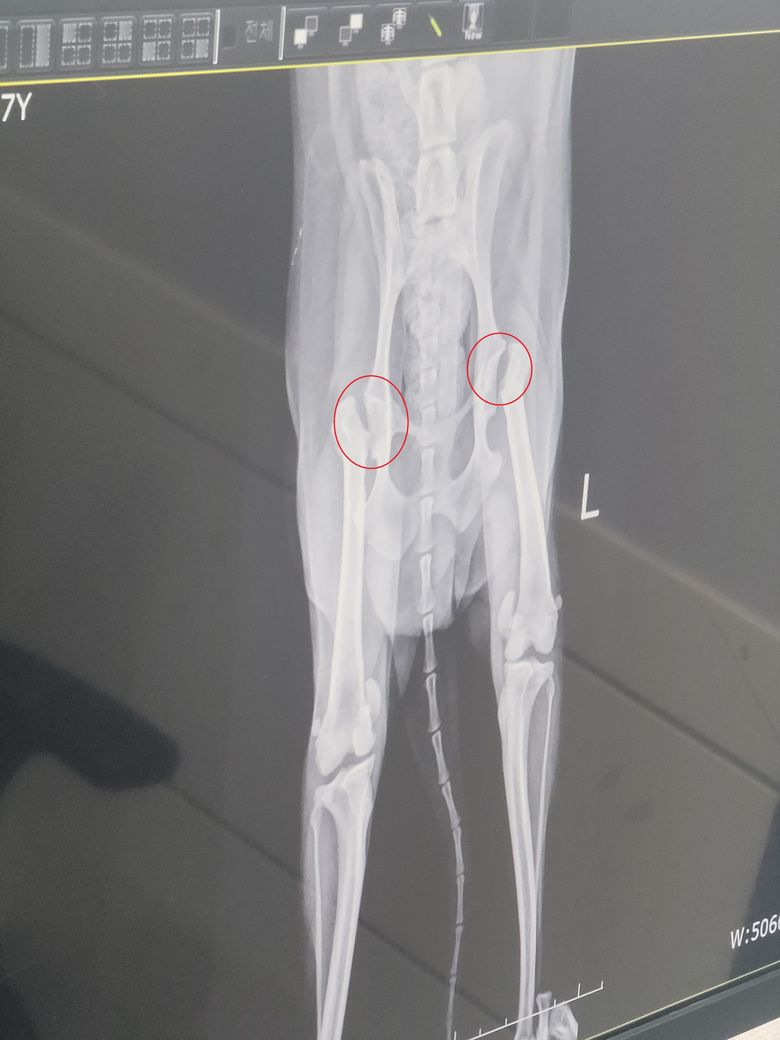

4월말에 고관절 이형성증으로 수술했습니다.

집에서 재활하는데 수술한 병원에서는 고관절 부위가 더 많이 벌어져야 한다고 재활을 더 열심히 해야한다고 하네요.

저정도 벌어지면 괜찮은건지, 아니면 벌어지는 것 상관없이 다른요소(근육량?)이 더 중요한지 궁금합니다.

3차원 구조를 2차원으로 잘라보는것이기 때문에 이 사진만으로 판단하는것은 부정확합니다. 그리고 양측 슬개골의 내측 탈구가 존재하고 이로인한 운동기능 저하 가능성이 있으니 주치의와 상담 후 슬개골 탈구 교정에 대한 처치 준비를 하시기 바랍니다.